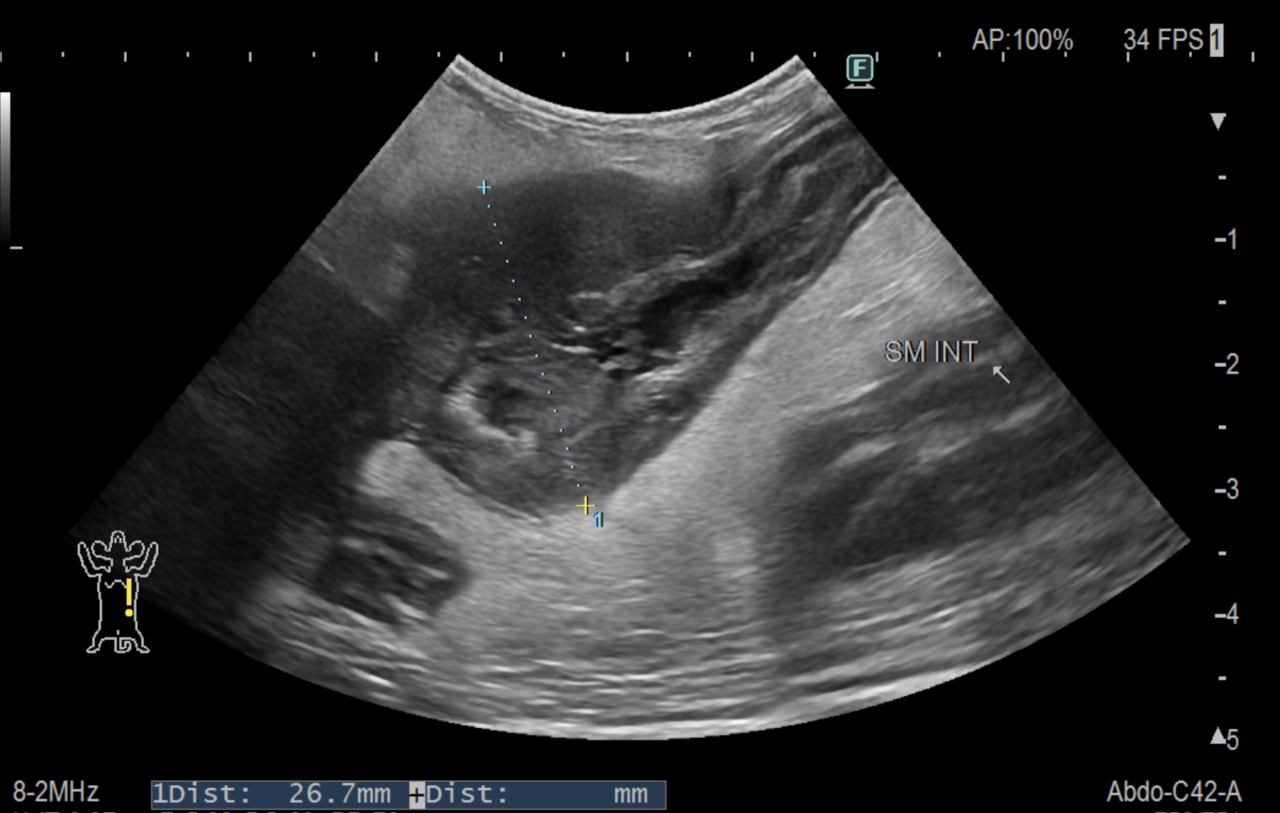

腹部エコー検査では小腸に腫瘍が確認され、腹部全体で腹膜炎が起きていました。

同時に行ったCT検査では腹腔内に遊離ガスが見られ、消化管穿孔と判断して手術を行いました。